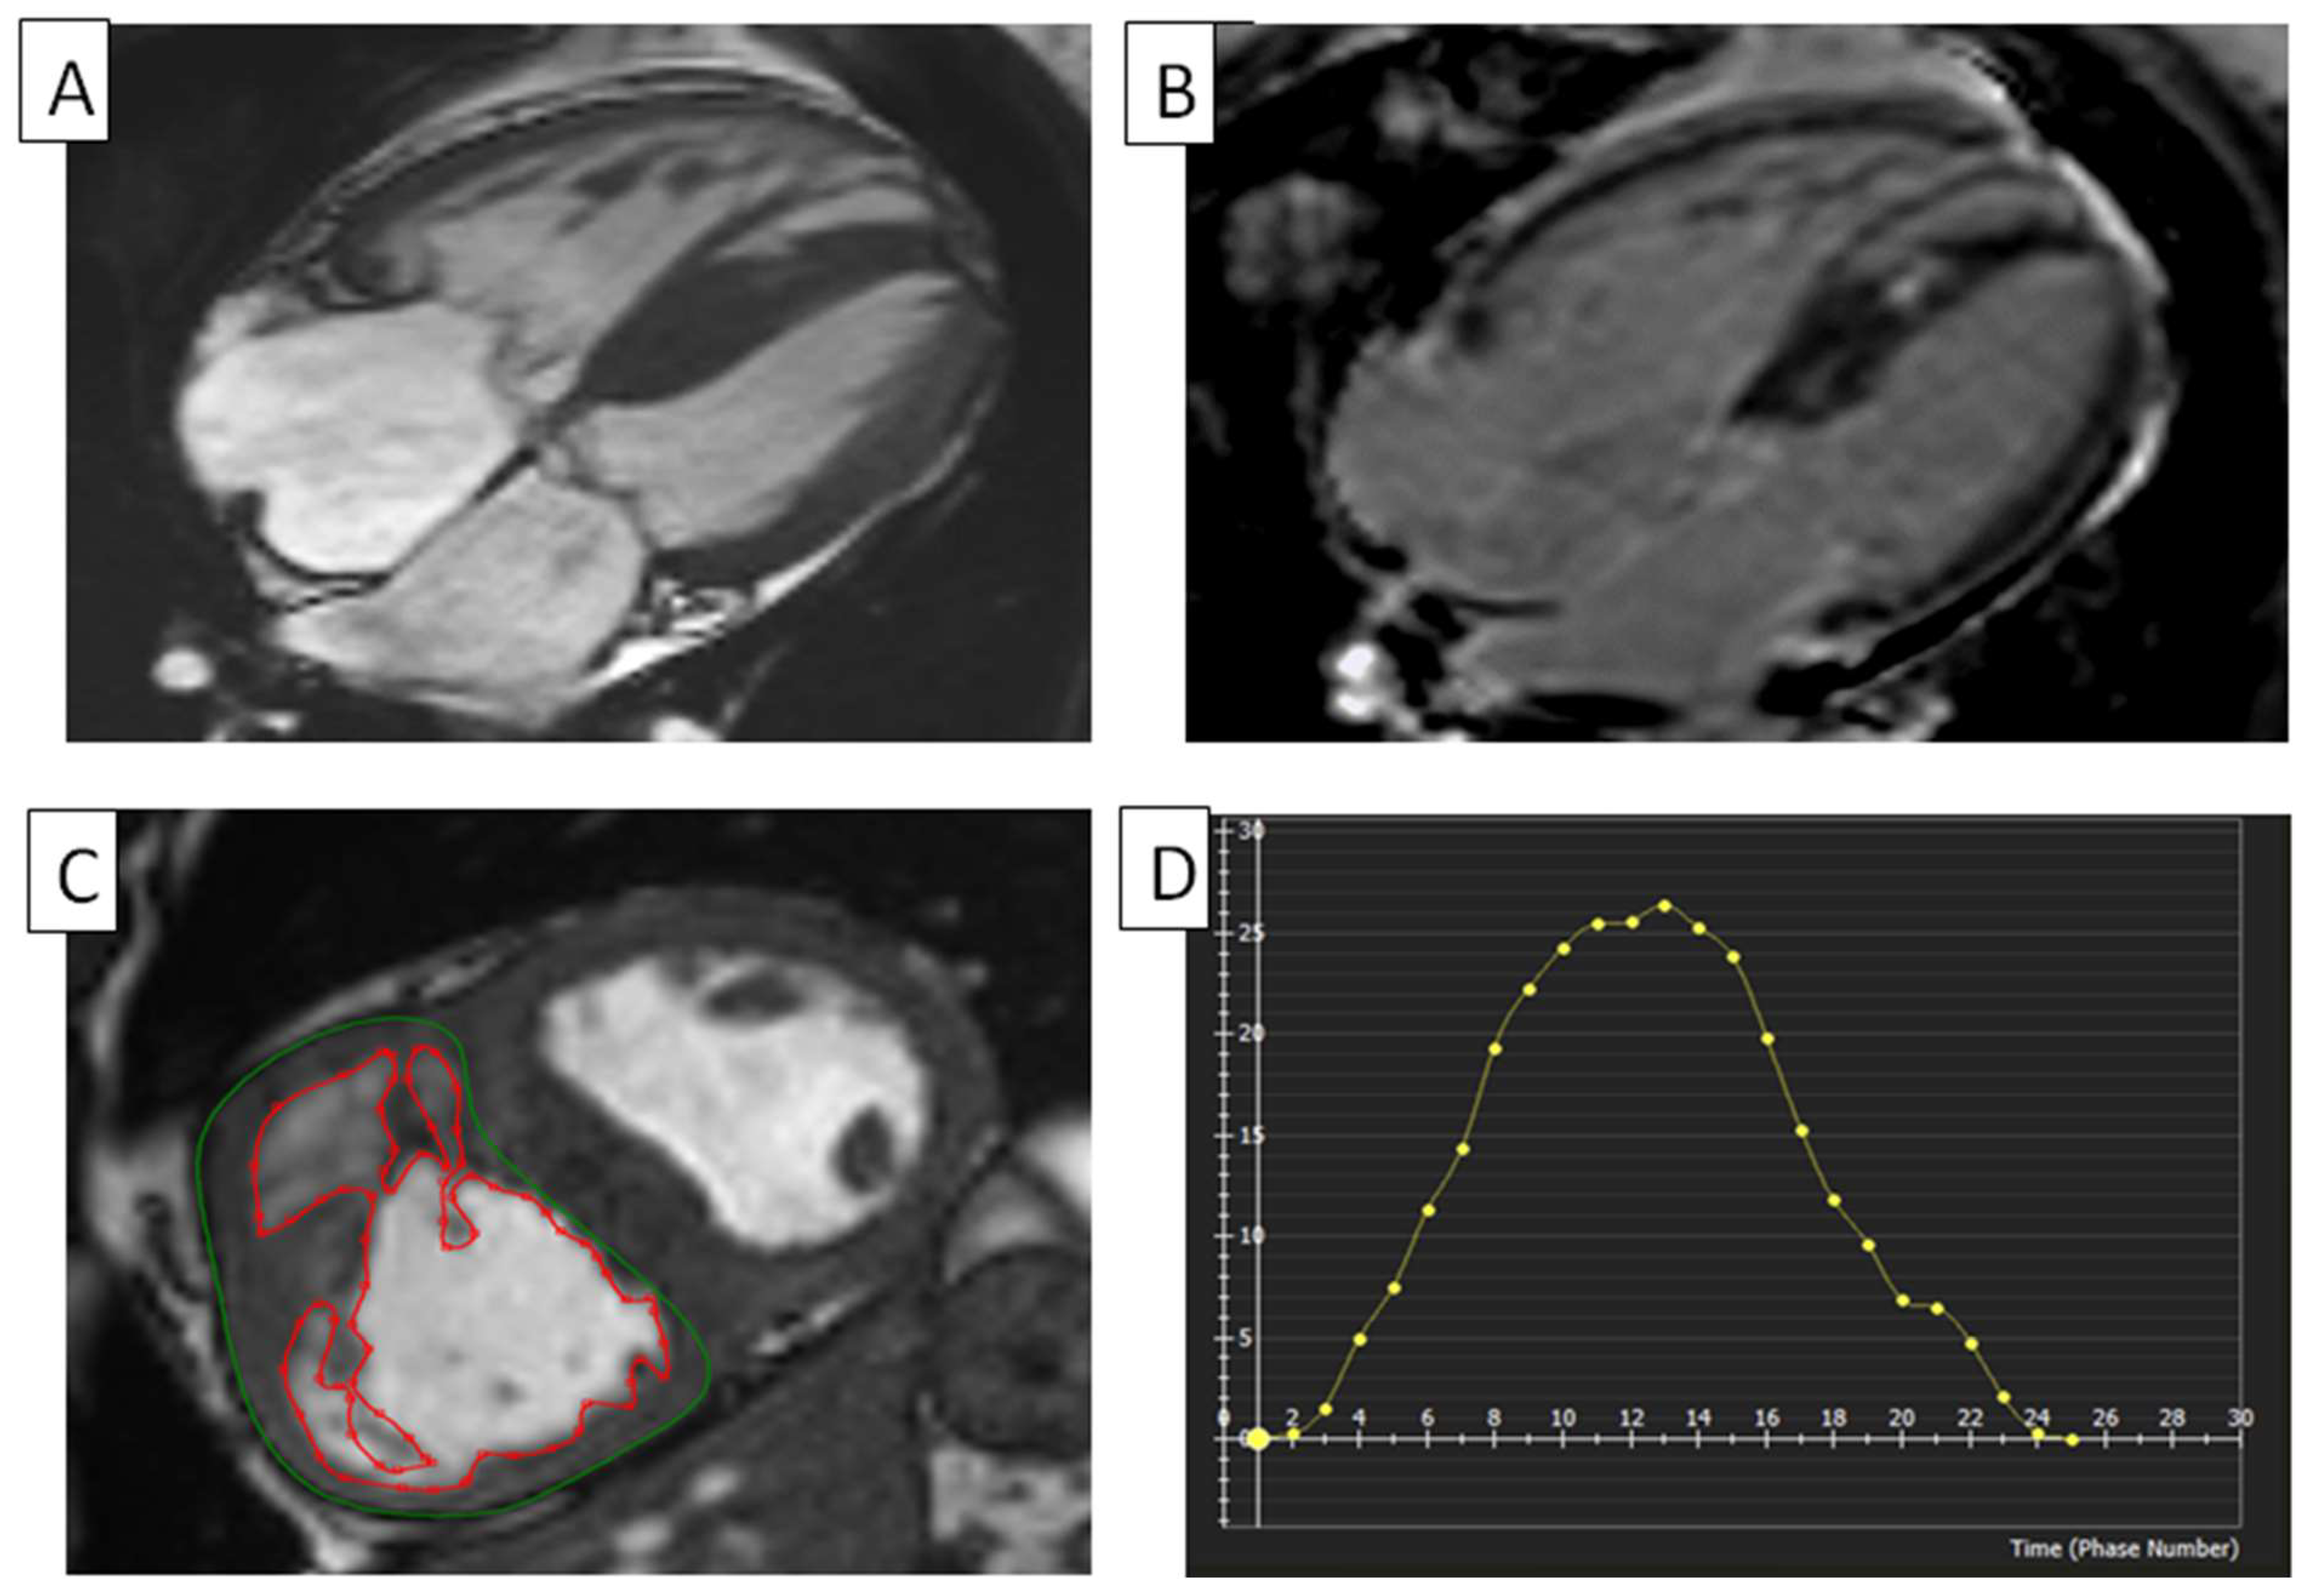

5.4. RV Infarction

- Kaandorp, T.A.; Lamb, H.J.; Poldermans, D.; Viergever, E.P.; Boersma, E.; van der Wall, E.E.; de Roos, A.; Bax, J.J. Assessment of right ventricular infarction with contrast-enhanced magnetic resonance imaging. Coron. Artery Dis. 2007, 18, 39–43. [Google Scholar] [CrossRef]

- Sharrack, N.; Das, A.; Kelly, C.; Teh, I.; Stoeck, C.T.; Kozerke, S.; Swoboda, P.P.; Greenwood, J.P.; Plein, S.; Schneider, J.E.; et al. The relationship between myocardial microstructure and strain in chronic infarction using cardiovascular magnetic resonance diffusion tensor imaging and feature tracking. J. Cardiovasc. Magn. Reson. 2022, 24, 66. [Google Scholar] [CrossRef]

- Bergamaschi, L.; Arangalage, D.; Maurizi, N.; Pizzi, C.; Valgimigli, M.; Iglesias, J.F.; Landi, A.; Leo, L.A.; Eeckhout, E.; Schwitter, J.; et al. Hepatic T1 Mapping as a Novel Cardio-Hepatic Axis Imaging Biomarker Early after STEMI. Eur. Heart J. Cardiovasc. Imaging 2024, 19, jeae256. [Google Scholar] [CrossRef]

- van Veelen, A.; Elias, J.; van Dongen, I.M.; Hoebers, L.P.C.; Claessen, B.; Ramunddal, T.; Laanmets, P.; Eriksen, E.; van der Schaaf, R.J.; Nijveldt, R.; et al. Recovery of right ventricular function and strain in patients with ST-segment elevation myocardial infarction and concurrent chronic total occlusion. Int. J. Cardiovasc. Imaging 2022, 38, 631–641. [Google Scholar] [CrossRef]

- Canton, L.; Suma, N.; Amicone, S.; Impellizzeri, A.; Bodega, F.; Marinelli, V.; Ciarlantini, M.; Casuso, M.; Bavuso, L.; Belà, R.; et al. Clinical impact of multimodality assessment of myocardial viability. Echocardiography 2024, 41, e15854. [Google Scholar] [CrossRef] [PubMed]